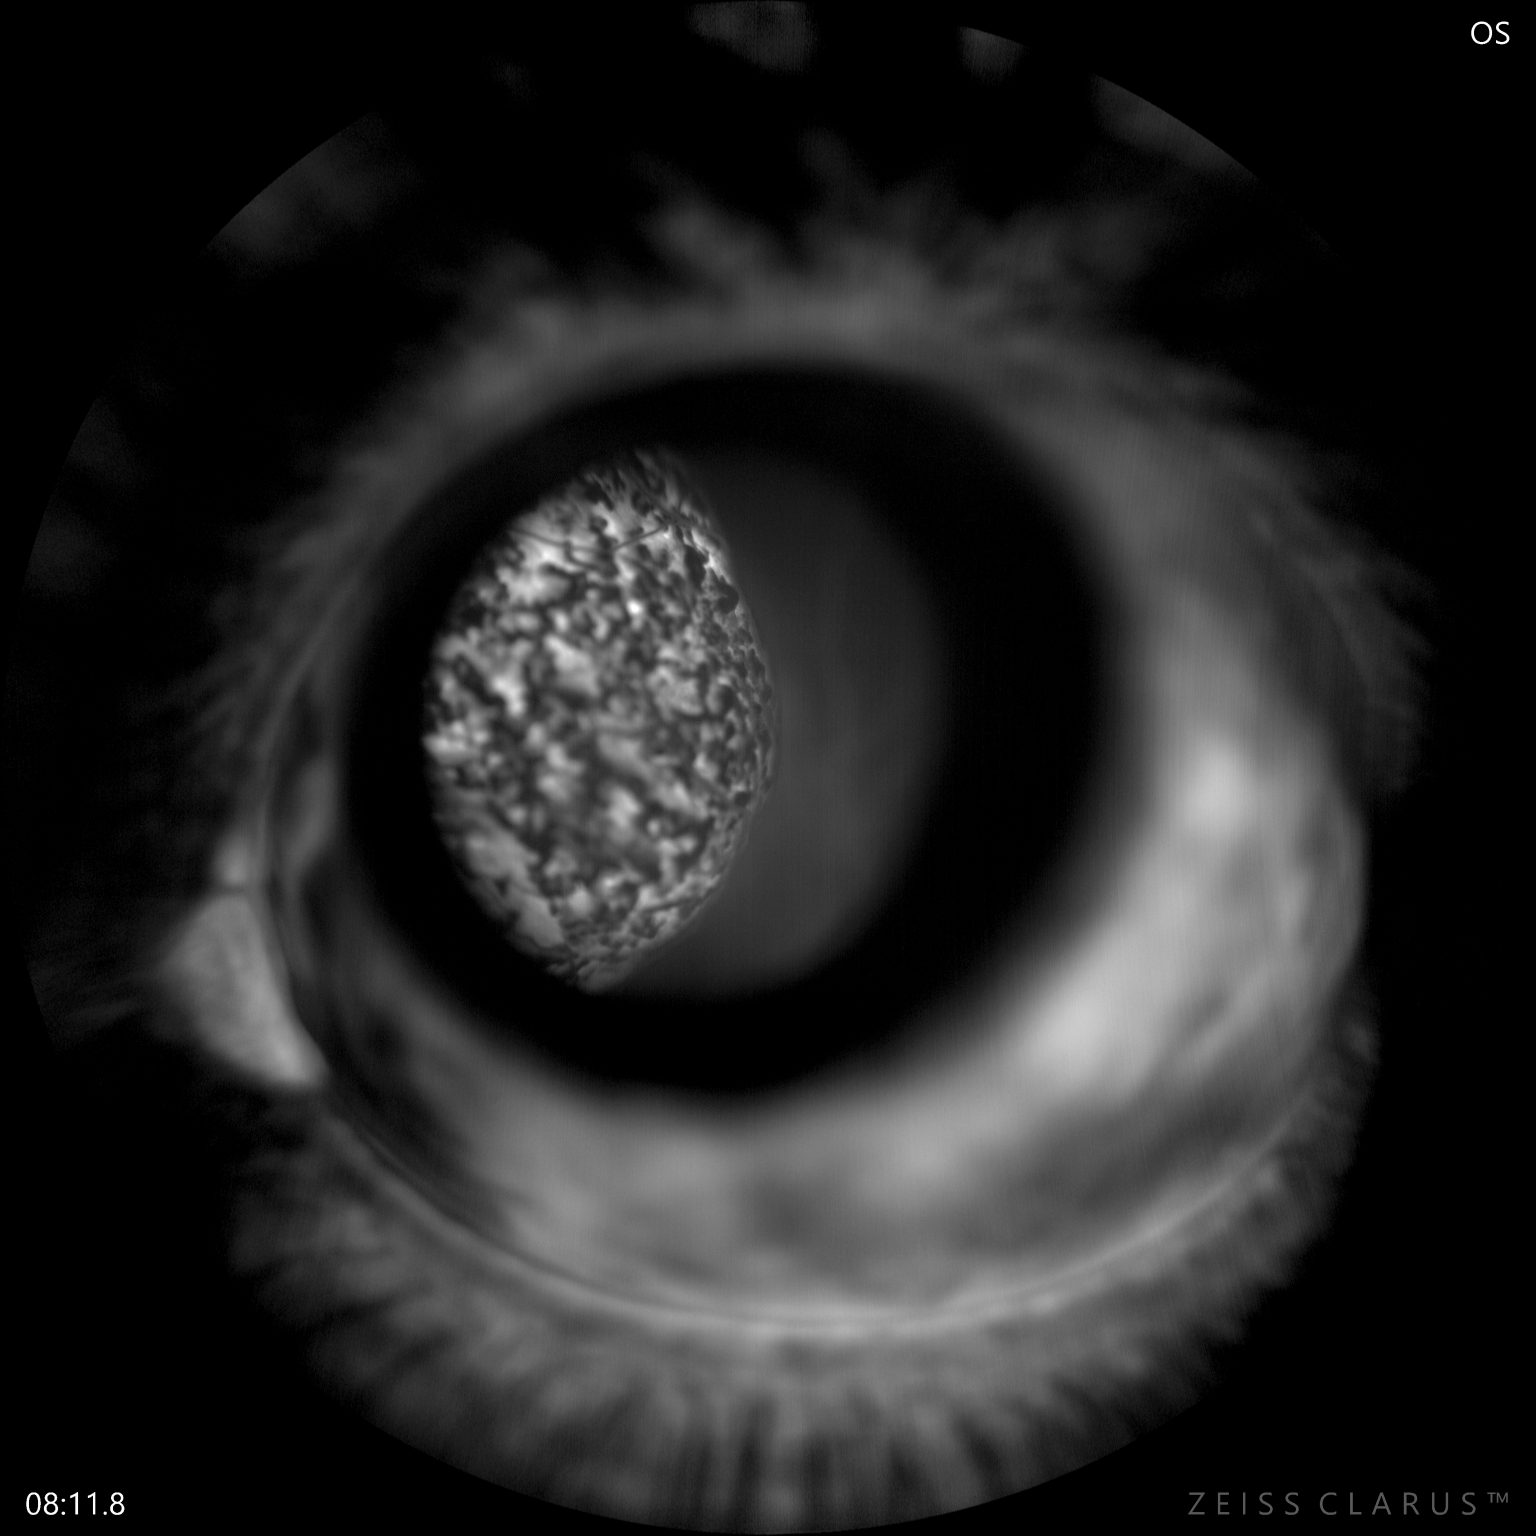

Choroidal Melanoma with Exudative Retinal Detachment - Raul Lince